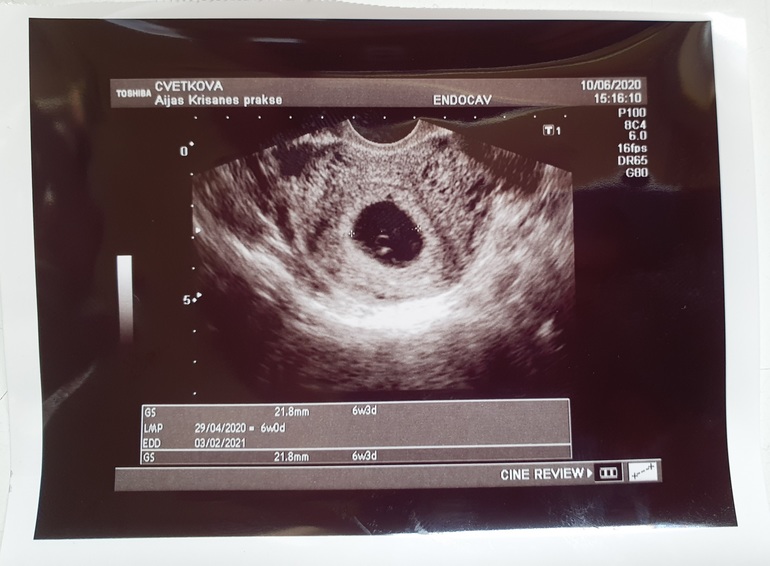

правда нам 6,3 .. 21.8мм

Похоже на беременность? Есть что-то?